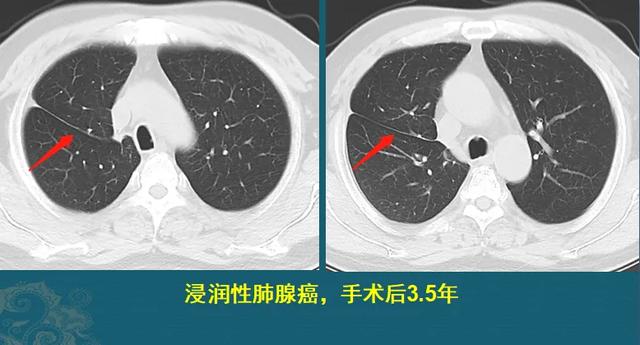

癌症从一开始就已经决定一个人的命运,治和不治都一样,是真的吗?插图1

这是一位30多岁男士,正是年轻力壮的好时候,也没什么症状,幸好单位组织体检,查出混合膜玻璃肺结节,ⅠA期肺腺癌。

癌症从一开始就已经决定一个人的命运,治和不治都一样,是真的吗?插图2

因为发现及时,手术完整切除,清扫淋巴结也没有发现转移,现在已经4年多了。

这种情况如果不治疗,很可能在未来一两年内进展到晚期,发生转移扩散,大大缩短寿命。